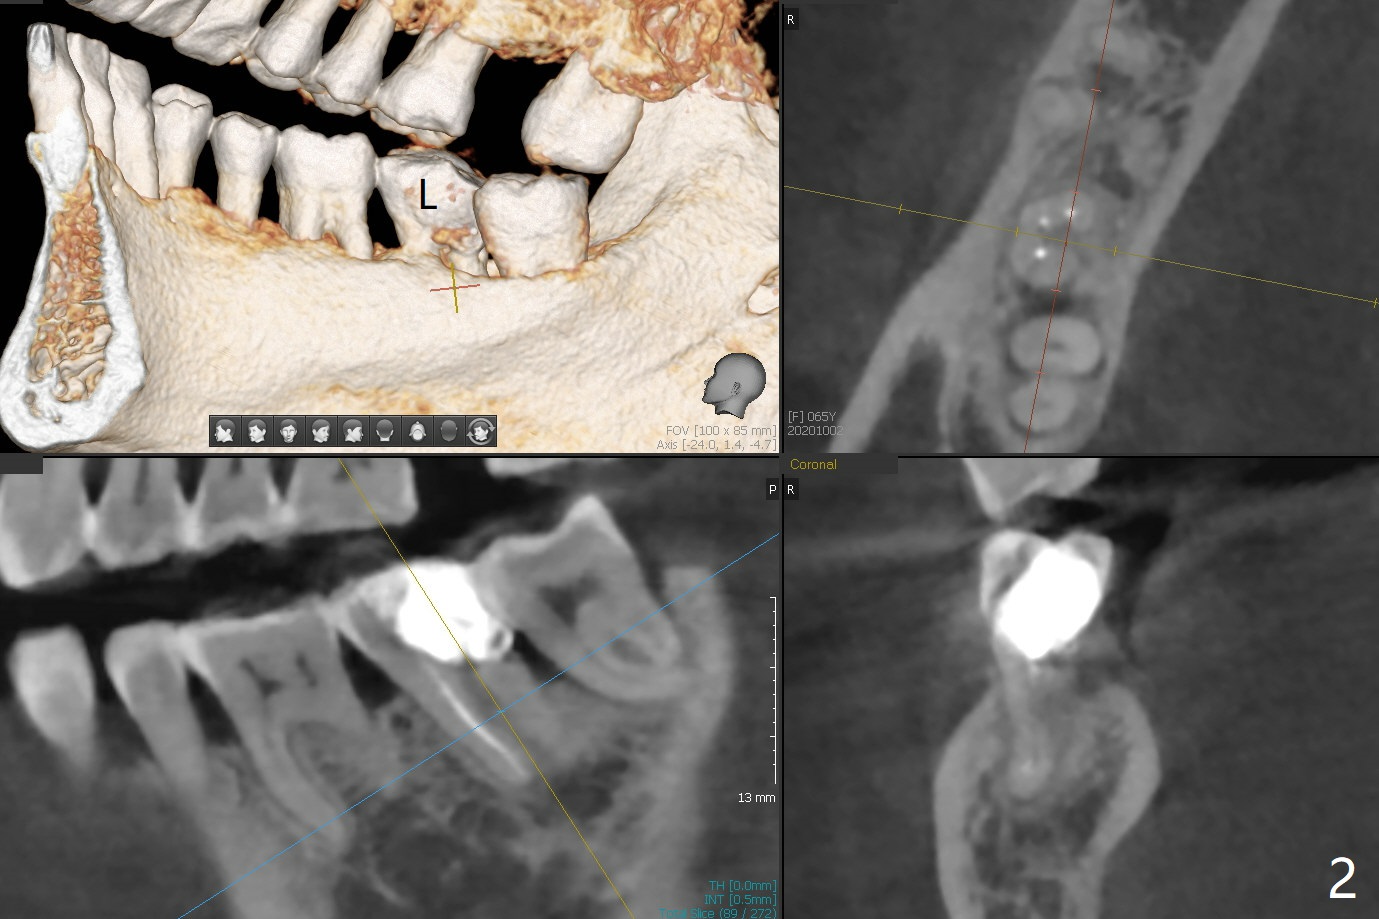

65岁女右下7远中舌侧龈下龋坏(图一,二),远中骨质吸收严重,植体应植入近中窝(图三:绿色),远中窝根部放置胶原塞(蓝色),冠部粘性骨粉(红色)。洁治邻牙,智齿近中面涂Endogain。